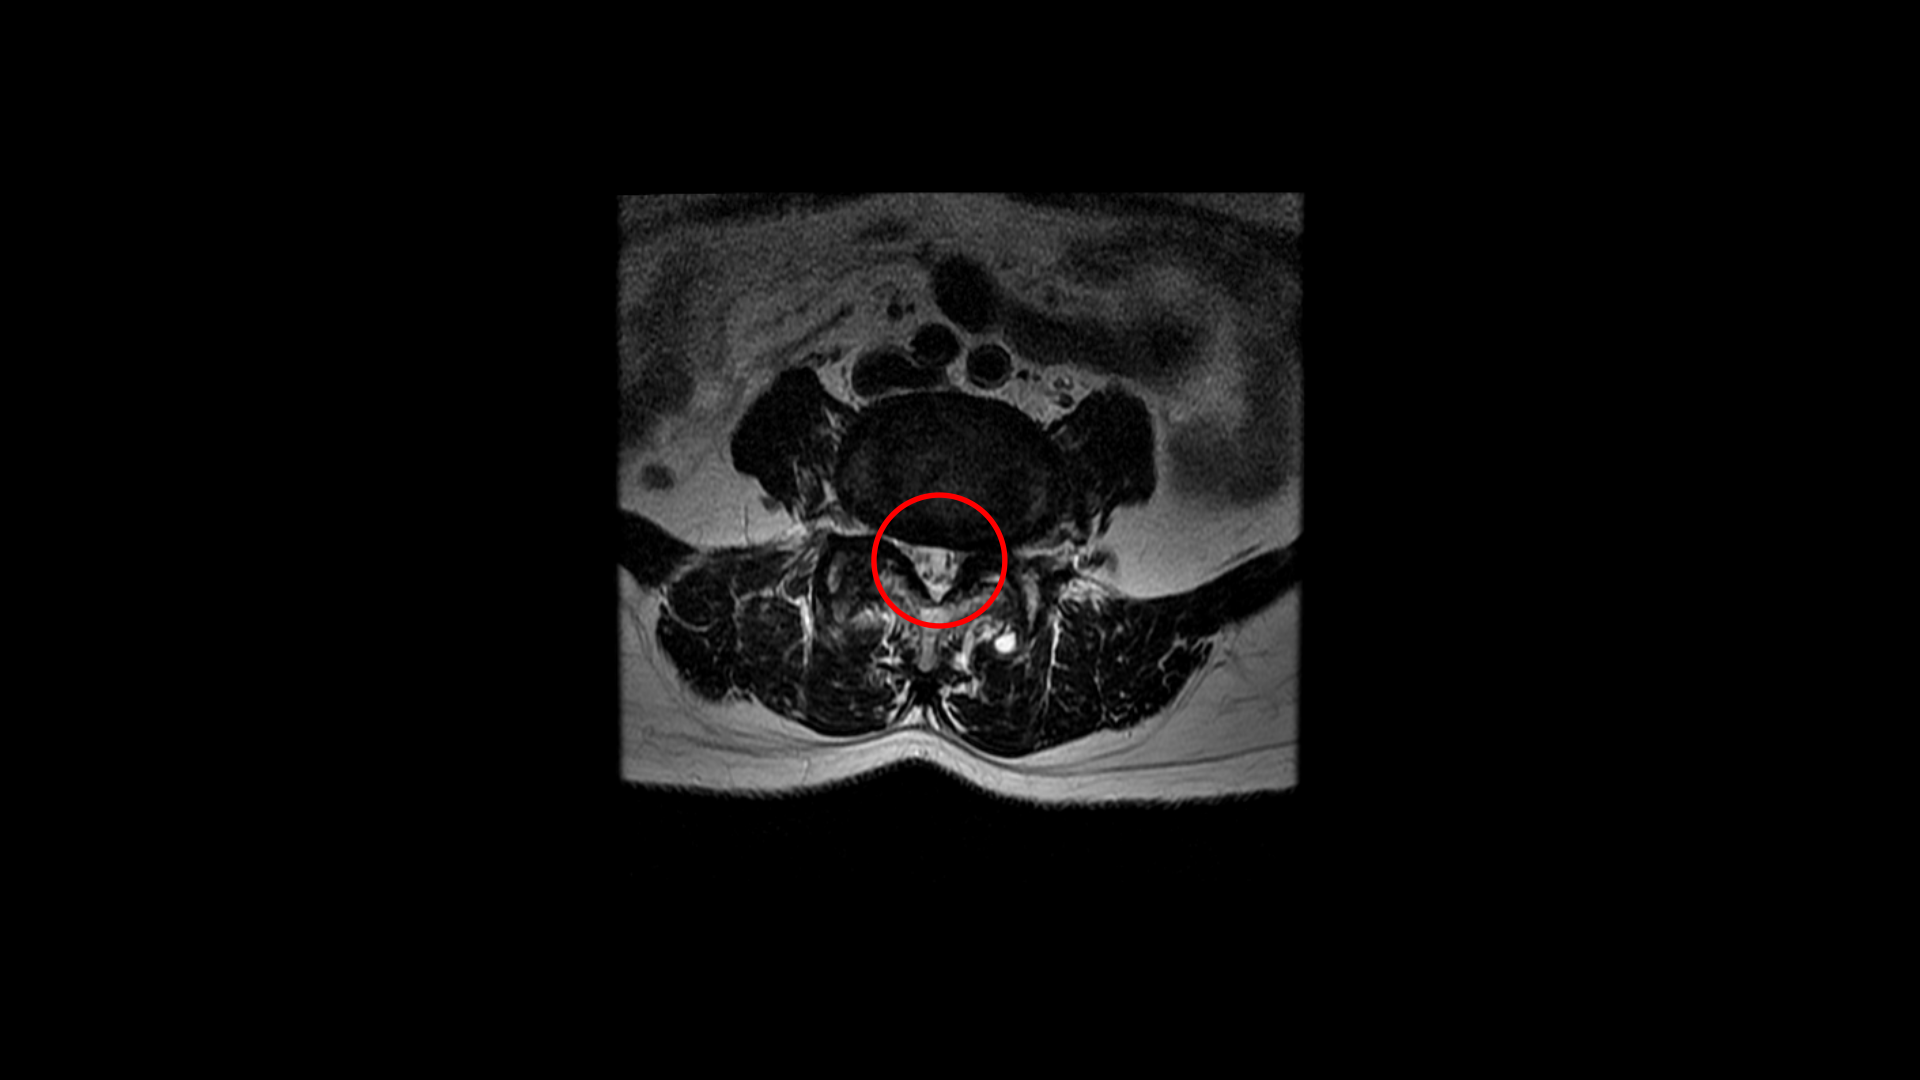

우선 이 환자분의 MRI를 함께 보겠습니다. 이 환자분의 척추에는 3번 4번과 4번 5번에 각각 1단계의 전방전위증이 있습니다.

그리고 4번 5번에도 왼쪽으로 퇴행성디스크와 후관절의 퇴행으로 신경 가지가 나가는 구멍이 좁아져 있습니다.

그런데 이 환자분의 제일 불편한 증상은 왼쪽이 아니고 오른쪽 엉치와 다리 증상입니다. 이분 오른쪽 신경 구멍들을 보면 전부 다 넓게 잘 열려 있습니다.

엉치와 다리 방사통을 일으킬만한 특별한 신경 눌림이 보이지 않는 것입니다. 그럼에도 불구하고 여러 마디의 전방전위증과 척추관 협착 그리고 디스크 탈출이 있으니까 그것을 원인으로 보고 신경 주사도 맞고 시술도 받으셨습니다. 그러나 별 효과는 없었습니다. 그리고 대학병원에서도 결국은 수술밖에 방법이 없다고 수술을 권유하였습니다.

이 환자분은 MRI에서 오른쪽에 신경 눌림이 심해 보이지 않는 상태에서 오른쪽에 심한 방사통과 함께 오른쪽 중둔근이 극심하게 뭉쳐있는 것이 확인되었습니다. 만일 이 근육들을 풀어서 하룻밤 사이에 방사통이 사라진다면 그건 명확히 근육성 방사통이었던 겁니다. 보통 단단하게 뭉쳐있는 근육에 의한 방사통이라해도 하루만에 치료가 되는 경우는 매우 드뭅니다. 특히 7년씩이나 방사통이 있었으면 근육이 뭉쳐도 정말 심하게 뭉쳐있을 거고 엉덩이 근육만이 아니라 허리 근육 및 다리 근육들도 다 뭉쳐있을 가능성이 높기 때문에 1-2주 정도 매일 4-5회 이상 다양한 방법으로 근육을 풀어주면서 쉬는 걸 반복하는, 즉 풀어주고 쉬고 풀어주고 쉬고 풀어주고 쉬고를 반복해야 극심하게 뭉친 근육이 풀립니다. 그래야 방사통이 사라지고 좋아지는 겁니다.